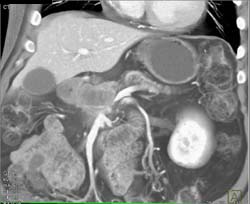

Lipoma in Tail of Pancreas